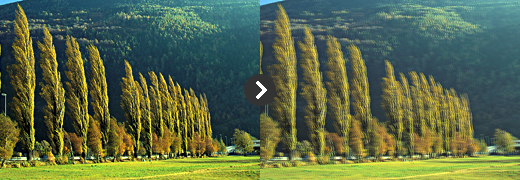

정상안 (물체가 선명하게 보인다)

정상안 (물체가 선명하게 보인다) -

백내장안 : 빛이 퍼진다 (물체가 흐릿하게 보인다)

백내장안 : 빛이 퍼진다 (물체가 흐릿하게 보인다)

하지만 자외선은 백내장을 유발하는 확실한 요인 중 하나입니다. 낮에 볕이 강한 밝은 곳에 나가실 때는

양산이나 창이 넓은 모자로 볕을 가려 눈을 보호하거나 선글라스를 사용하는 것을 권장합니다.

또한 강한 자외선의 노출은 노령층의 시력에 치명적인 황반변성의 유발 인자도 되기에

가급적 햇볕에 나갈 때는 선글라스가 필수입니다.